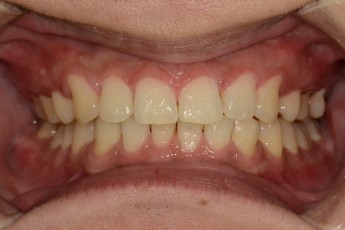

BEFORE & AFTER